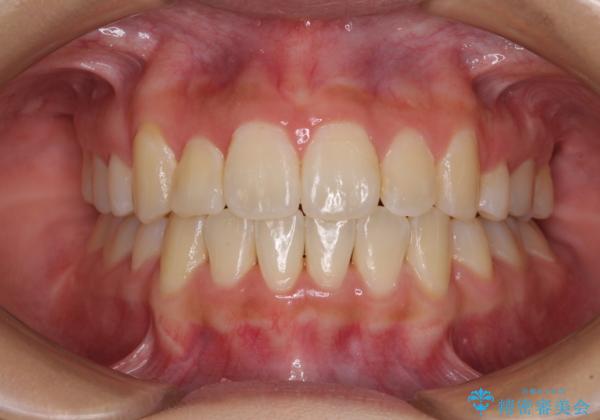

移動量が多かったため、治療期間は通常より半年~1年ほど長くかかりましたが、上下の正中をほぼ同じ位置にまで移動させることができました。